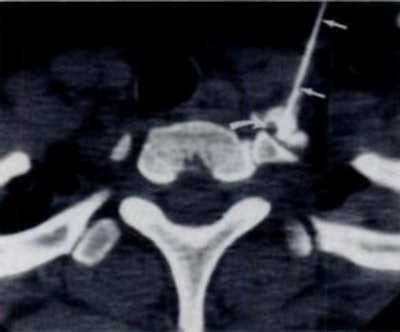

Исследователи провели исследование, в котором приняли участие 54 пациента, направленные отоларингологом после как минимум шести месяцев паросмии после COVID. Все прошли процедуру блокады звездчатого ганглия; команда использовала компьютерную томографию, чтобы расположить спинальную иглу 25-го калибра у основания шеи и ввести анестетик в звездчатый ганглий.